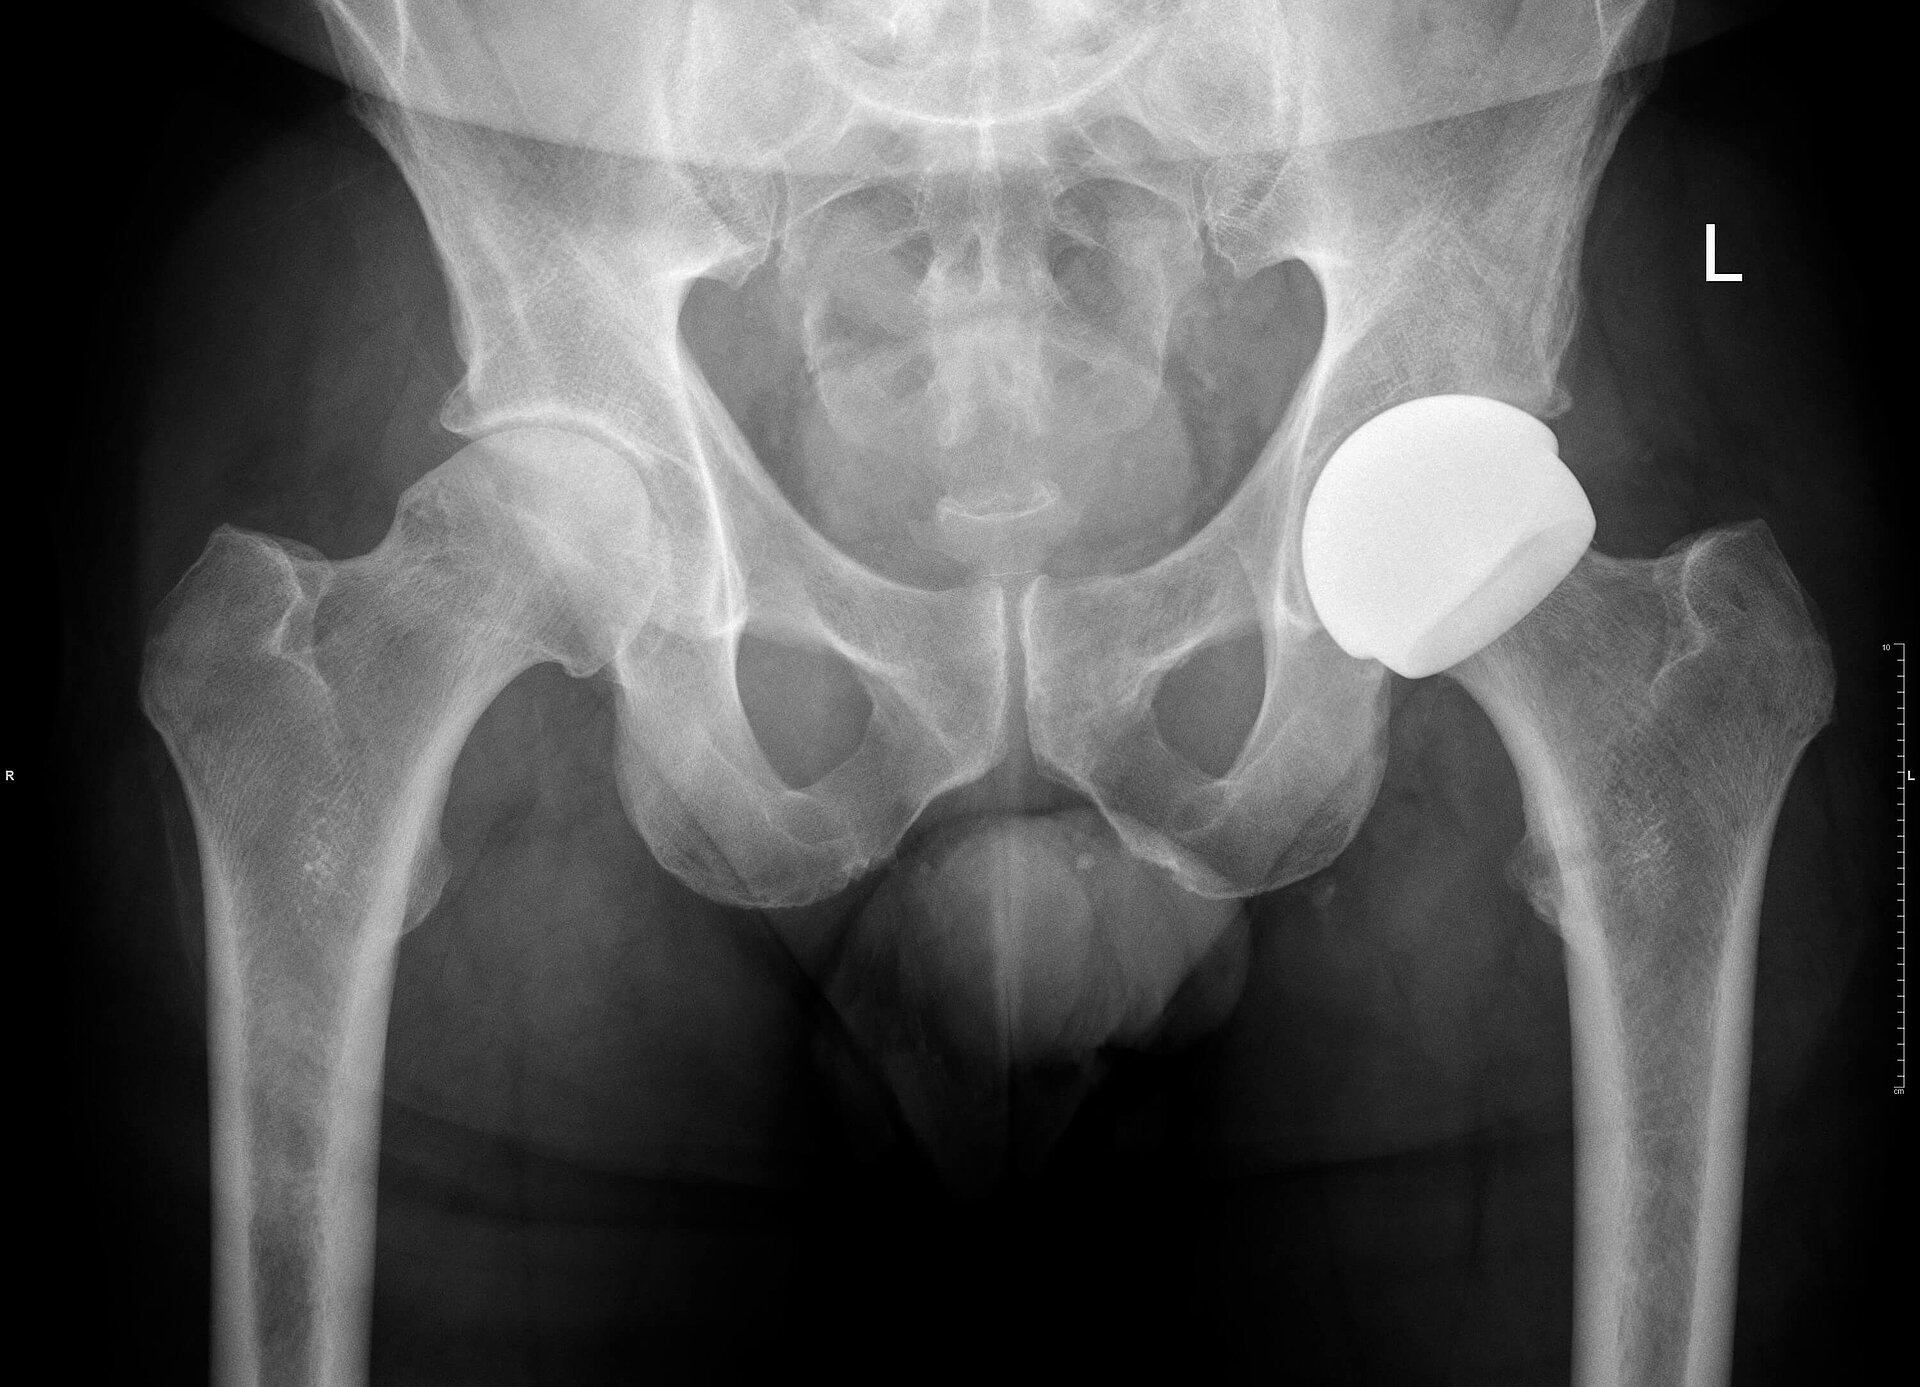

At the time of surgery, via a standard posterior approach, using exactly the same exposure and release as required for a metal-on-metal hip resurfacing, a ReCerf® device was implanted. The 56mm colour-coded socket was implanted using a specifically designed acetabular insertion device, used alongside the standard ADEPT® socket insertion handle and alignment jig. Socket position was targeted at between 35 and 40 degrees of abduction with anteversion matching the native socket and the transverse acetabular ligament, typically around 15 degrees.

The standard ADEPT® medial referencing jig was used to position a guide wire into the femoral head and neck, determining bone preparation and component position. Again, the same instrumentation used for the ADEPT® device is used with ReCerf®. With preparation complete, a compatible and similarly colour-coded 50mm femoral component was cemented in place, using standard cement fixation and impaction technique to the established ADEPT® metal-on-metal device. (As such the ReCerf® concept uses of the majority of the ADEPT® metal-on-metal instrumentation and would therefore provide the surgeon with the opportunity to determine bearing surface material with flexibility intraoperatively.)